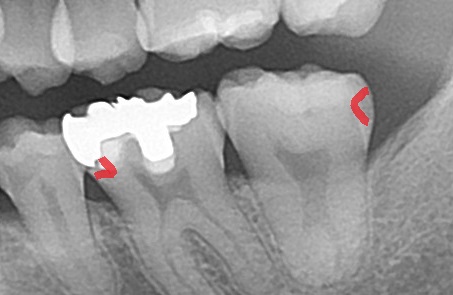

まずはエックス線検査を行い、歯の内部の状況を確認します。

銀歯が白く写っています。

ここから分かることは、

銀歯の中が虫歯になっていること。

さらに奥の歯も虫歯になっていることが分かります。

エックス線写真では虫歯が黒く写ってきます。

どこかというと、

赤く示した箇所が黒く抜けて写っています。

つまり、今回は銀歯を、もう一つ奥の歯の虫歯の治療を行います。